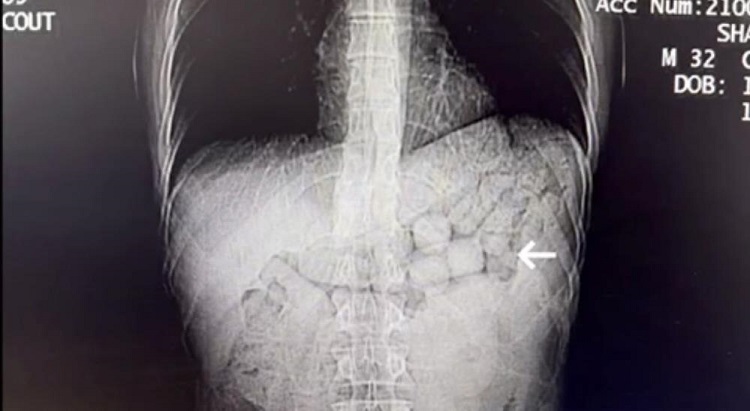

TOMOGRAFİDE GÖRÜNTÜLENDİ

Bahse konu şahısların çekilen tomografi görüntülerinde, mide ve bağırsak bölümlerinde yabancı cisimlere rastlandı.